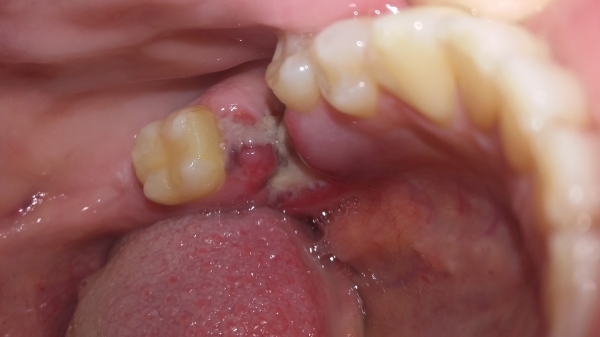

В понедельник мне удалили 26 зуб. Снимок показал воспаление и то, что корни расколоты. При удалении зуб крошился и был сильный запах гноя. Врач не прописал антибиотики и запретил чем-либо полоскать. Пью обезболивающие, припухла щека. Очень болит десна соседнего зуба, такое ощущение, что его тоже сдвинули с места.

Белый, неприятно пахнущий налет, это процесс естественного заживления лунки.

Десна на соседнем зубе была задета тоже. Поэтому не стоит переживать, если симптомы такие как: температура, боль, отек, не начнут сильно увеличиваться.